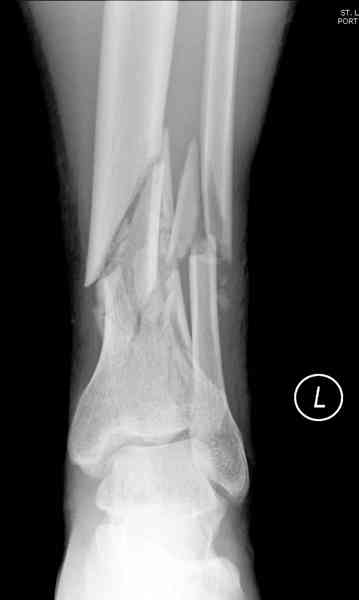

При высокоскоростных переломах редко можно встретить изолированную травму пилона, и в моей практике изолированные травмы большая редкость, поэтому, как дополнение к обсуждаемой теме, решил представить свежий, двухдневной давности случай.

Предыдущей сменой до 4:00 утра по поводу открытого перелома бедра, тибиал плато, пилон и надколенника сделана операция.

Пострадавшему 21 г., травма скоростная, после I&D с расширением раны, на бедре сделана операция ретроградным интрамедуллярным штифтом, остеосинтез с частичной резекцией надколенника и ушивание собственной связки.

На голень наружный фиксатор, рану на бедре ушили (рана была изнутри кнаружи всего 2 см). По протоколу травматических больных, до операции обследован ангиографически, (у больного дистально не смогли определить пульсацию) сосудистый хирург подтвердил проходимость на всем протяжении магистрального сосуда нижней конечности по снимкам ангиограмм.

КТ пилона имеем.